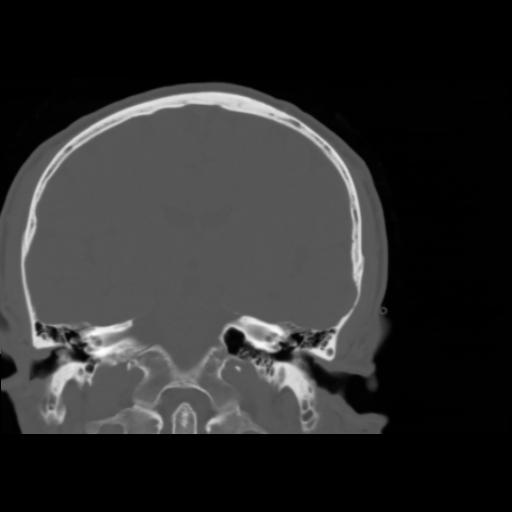

5 CEREBRO,,Coronal,3.000,CEREBRO,Coronal,